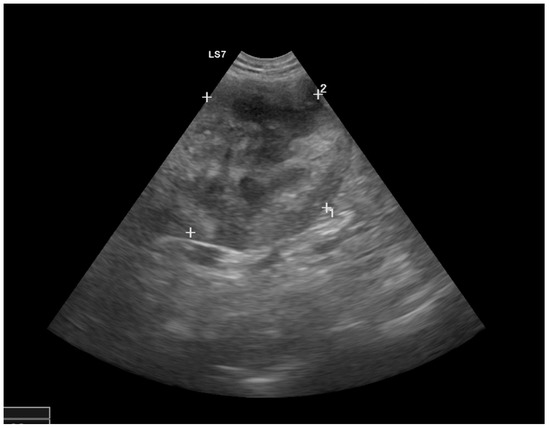

1. Case Presentation